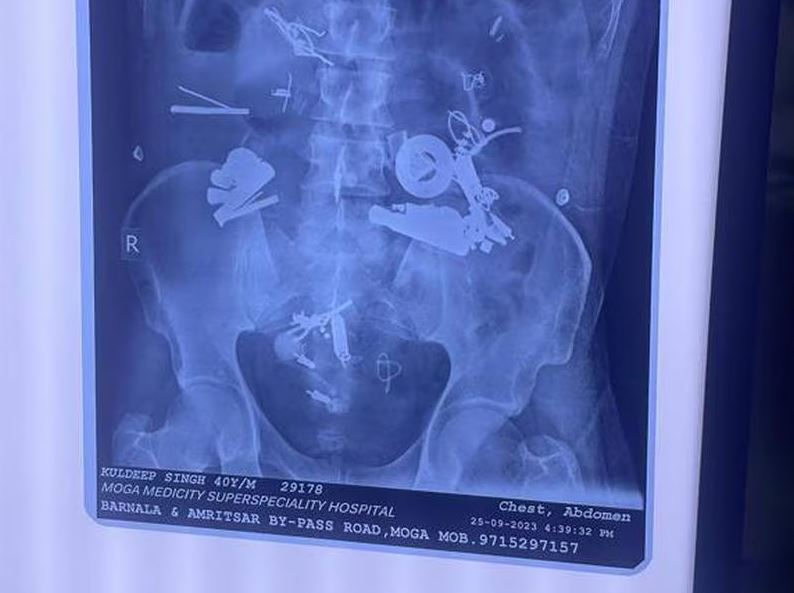

پزشکان در ایالت پنجاب در شمال هند پس از کشف و خارج کردن سمعک، دستبند، پیچ و مهره و سنجاق قفلی در میان ۱۵۰ شئ خارجی در معده بیمار تحت عمل جراحی قرار گرفته بهت زده شدند. این مرد ۴۰ سال روز دوشنبه هفته گذشته با ابراز گلایه از درد شدید معده و حات تهوع در بیمارستان مدیسیتی در ناحیه موگا در ایالات پنجاب در هندوستان بستری شد.

پزشکان با بررسی تصاویر گرفته شده با استفاده از اشعه ایکس متوجه شدند اشیاء فلزی در داخل بدن آن بیمار وجود دارند. آنان بلافاصله عمل جراحی را آغاز کرده و در جریان عمل جراحی سه ساعته سمعک، دستبند، پیچ و مهره، سیم، قفل، دکمه و سنجاق قفلی از شکم او بیرون آوردند. این مرد روز پنجشنبه پس از عمل جراحی بر اثر سپسیس* جان اش را از دست داد.

دکتر “اجمر کالرا” مدیر بیمارستان گفت:”زمانی که گزارشهای اشعه ایکس را دریافت کردیم بهت زده شده بودیم. محموعهای از اجسام خارجی در شکم او وجود داشتند. پس از جراحی ما ۱۵۰ قلم شئ از جمله دستبند، زیپ، میخ و پیچ و مهره پیدا کردیم. بیمار نزدیک به یک هفته درد داشت. ما از دستگاه تنفس مصنوعی برایش استفاده کردیم، اما نتوانستیم وی را نجات دهیم. او دچار تورم ناحیه شکم شده بود که در نهایت باعث سوراخ شدن شکم اش و در نهایت سپسیس شد و به همین خاطر جان اش را از دست داد”.